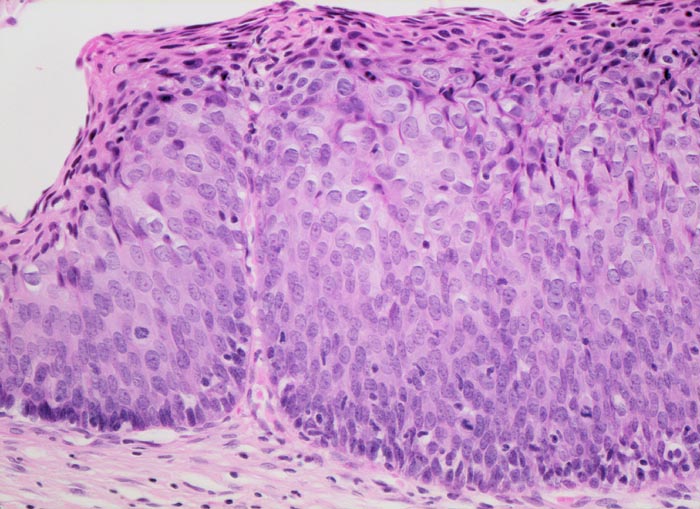

Die HPV Infektion kann gelegentlich aufgrund zytopathischer Effekte in den infizierten oberflächlichen Plattenepithelzellen erkannt werden. Die zytopathisch veränderten Zellen nennt man Koilozyten. Koilozyten weisen einen hellen perinukleären Hof und einen verdickten peripheren Zytoplasmasaum auf (> 5546) (> 5547). Sie enthalten einen oder mehrere hyperchromatische dunkle Zellkerne. Ein flaches Areal mit zytopathisch veränderten Plattenepithelzellen wird als flache kondylomatöse Läsion bezeichnet (> 1093). Die LSIL ist gekennzeichnet durch Zellatypien und Mitosefiguren im unteren Epitheldrittel, während die oberen Zweidrittel des Epithels ausreifen (Verkleinerung der Zellkerne und vermehrtes Zytoplasma in den oberflächlichen Zellen). Bei der HSIL breiten sich die Zellatypien und Mitosefiguren auf das mittlere (CIN II) und obere Drittel (CIN III, Cis) des Epithels aus. Die oberflächlichen Zellen des Carcinoma in situ reifen nicht mehr aus und zeigen entsprechend eine hohe Kern-Plasmarelation.

• Carcinoma in situ der ektozervikalen Schleimhaut und des metaplastischen Plattenepithels im Bereich der Transitionalzone.

• Einwachsen des Carcinoma in situ in vorbestehende endozervikale Drüsenschläuche.

• Zylinderepithel der endozervikalen Drüsen ohne Dysplasie. Das sollte der Kliniker dem Pathologen mitteilen: